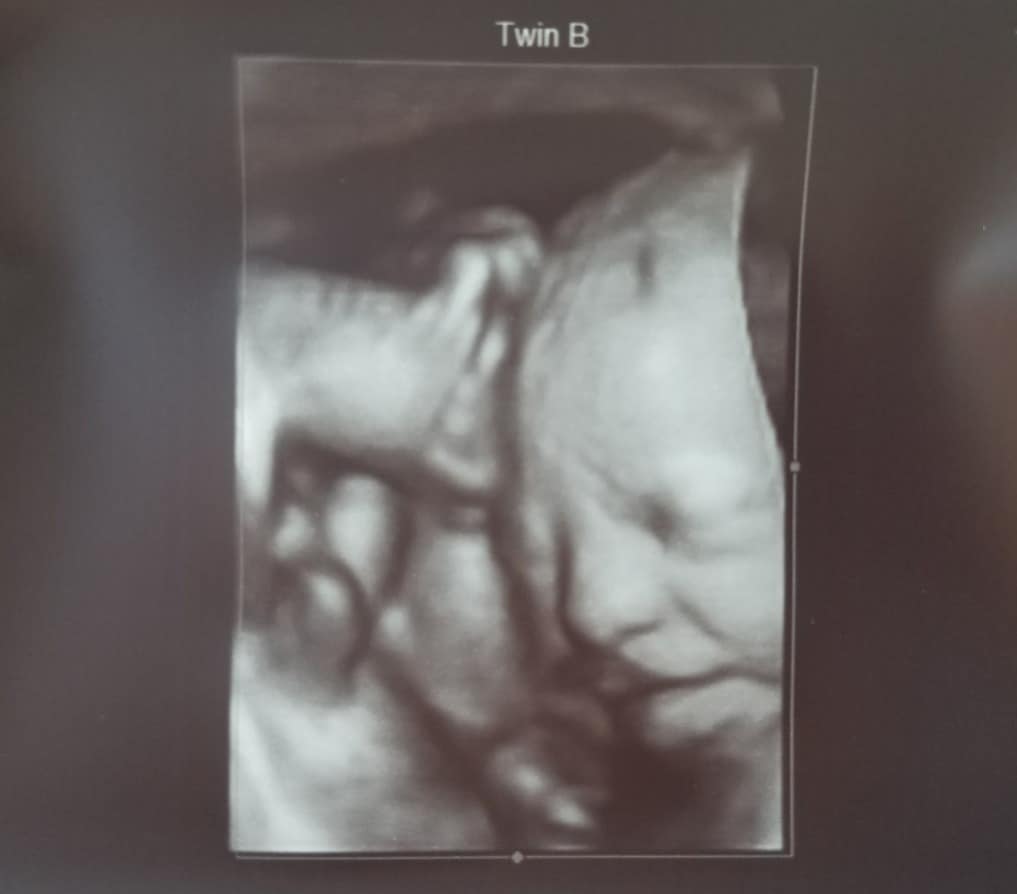

Ultrasound Photos at 30 Weeks Pregnant With Twins